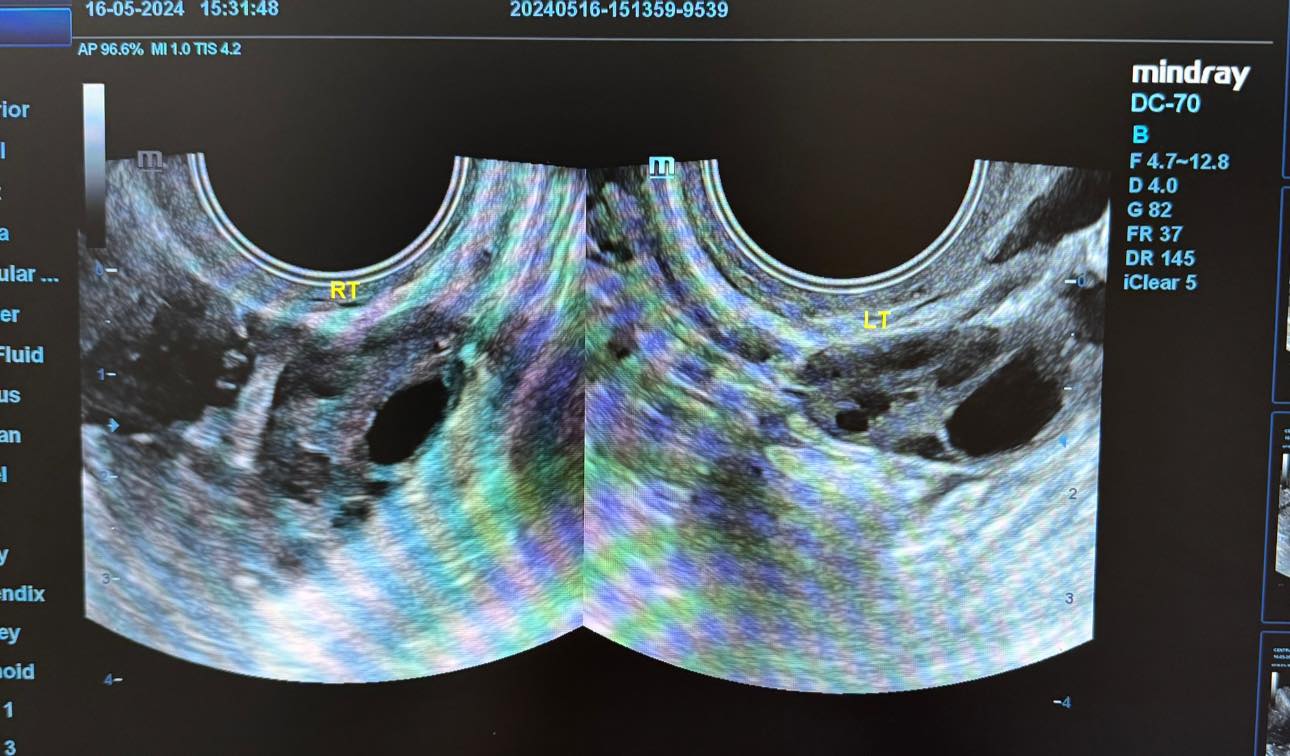

O tânără de 21 de ani a mers la medic din cauza unor dureri și a dereglărilor menstruale și a avut un șoc. A aflat că are un chist hemoragic de cm la nivelul ovarului drept. Aceasta a mers la medicul Alexandra Ciobanu, în luna ianuarie, cu „dereglări ale ciclului menstrual și dureri pelvine”.

Doctorul i-a dat să urmeze un tratament pentru cinci luni, pe care aceasta l-a urmat cu strictețe, iar rezultatele nu au întârziat să apară.

„Diagnosticul corect împreună cu respectarea indicațiilor terapeutice sunt esențiale, de aceea vă sfătuiesc să mergeți la medic atunci când corpul vă transmite semnale de alarmă. Diagnosticul întârziat al unor afecțiuni poate conduce la complicații serioase”, este mesajul medicului.